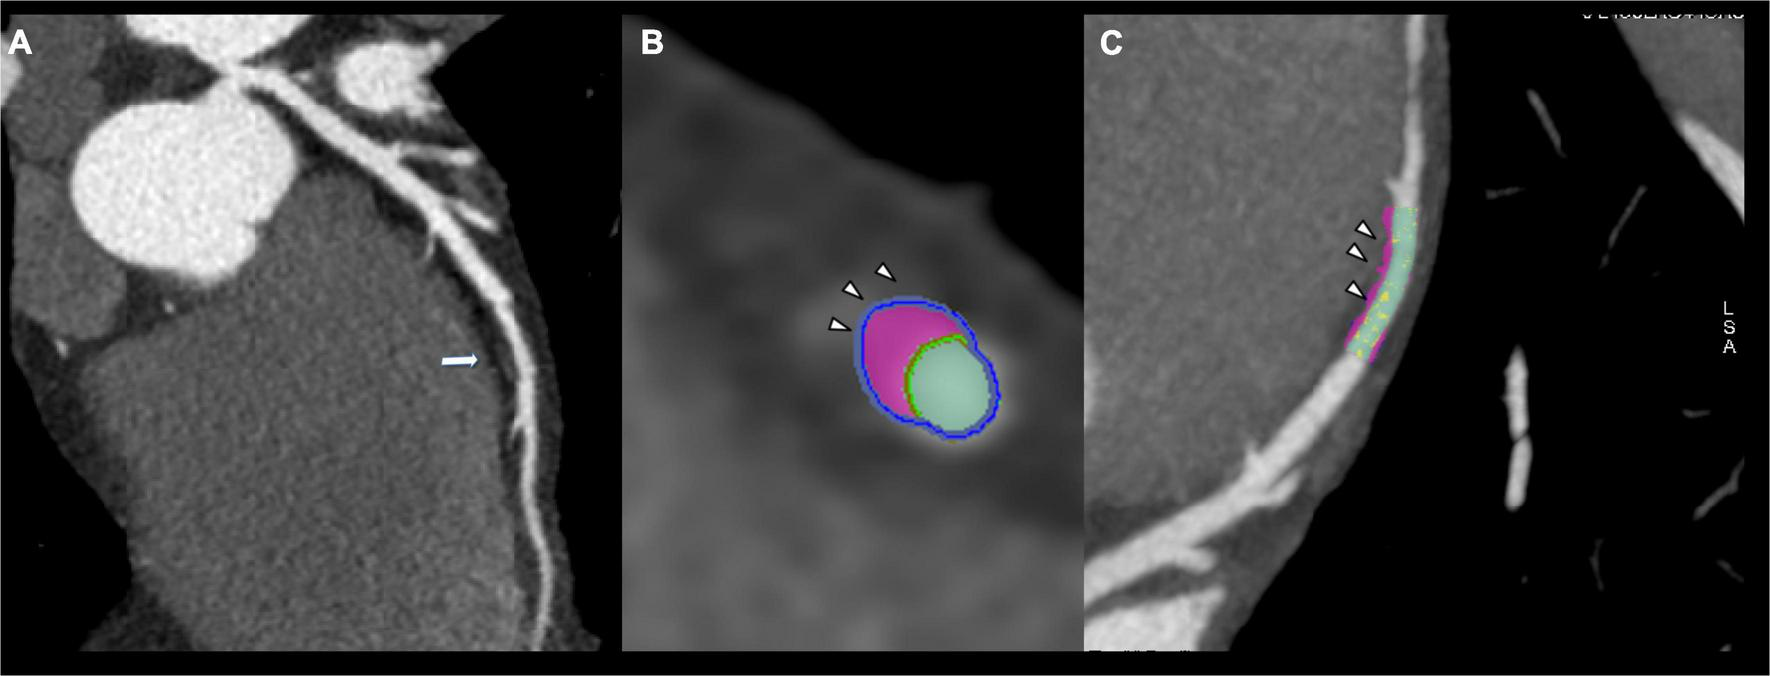

FIGURE 1

Thirty-six years old male showing fibrofatty plaque with positive remodeling on mid-lef anterior descending artery (arrow, A). Plaque analysis confirmed the fibrofatty composition of coronary plaque demonstrating the positive remodeling (arrowhead, B,C).